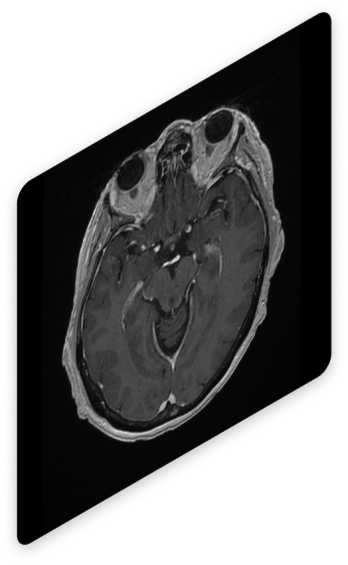

Visualización de las Adquisiciones

Revisa las imágenes adquiridas desde un visor profesional

El simulador incluye un visor integrado que permite interactuar con las imágenes, explorar cortes anatómicos y obtener una comprensión detallada de los resultados.